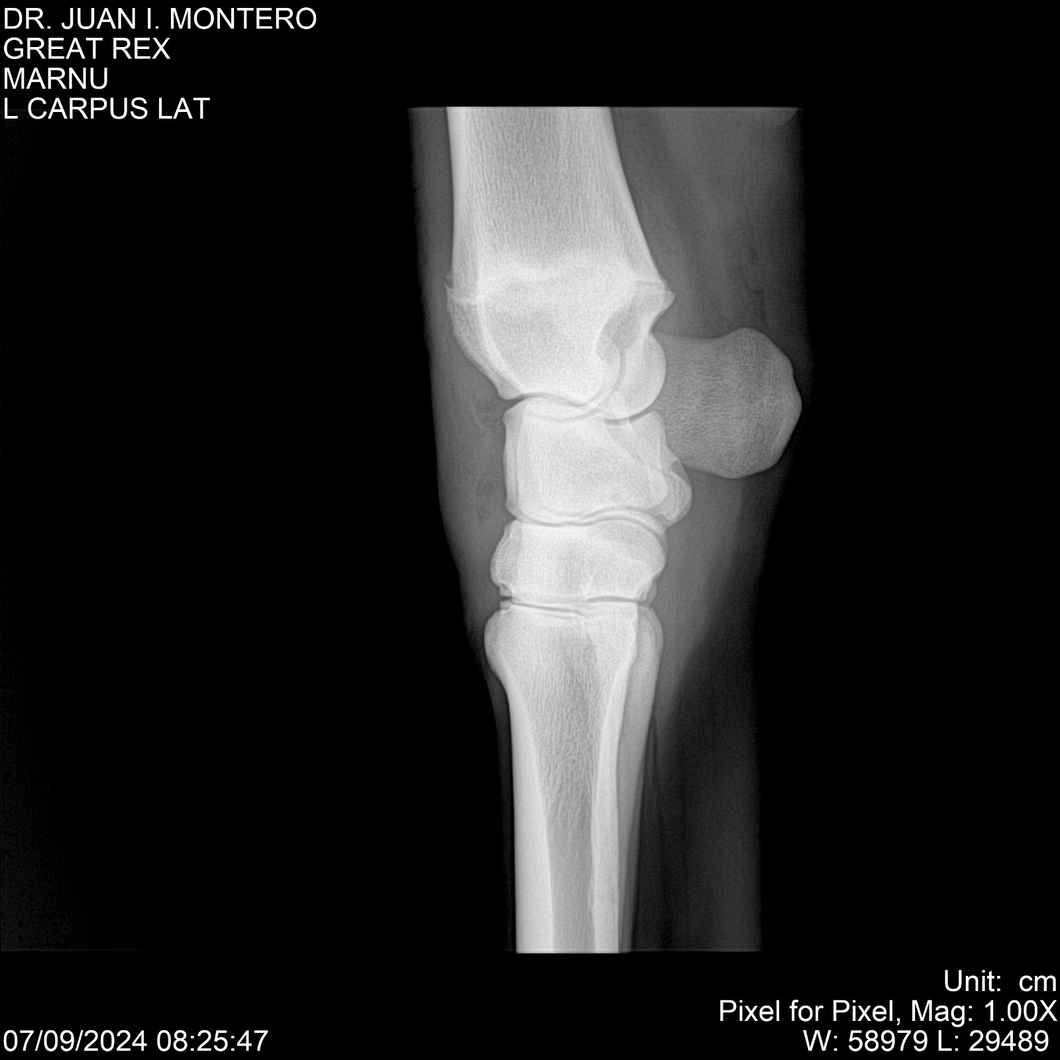

LOTE 4, GREAT REX Lote Anterior Volver al remate Lote Siguiente Ficha Contacto Montevideo - Ficha del Lote Identificador: #282518 Categoría: Yeguarizos Montevideo - 66 Visualizaciones ClicData Contacto Empresa: Abelenda N. R., Walter Hugo Nombre*: Teléfono* : E-mail* : Mensaje Enviar Registrese gratis Este contenido Exclusivo está disponible sólo para usuarios registrados Ingresar